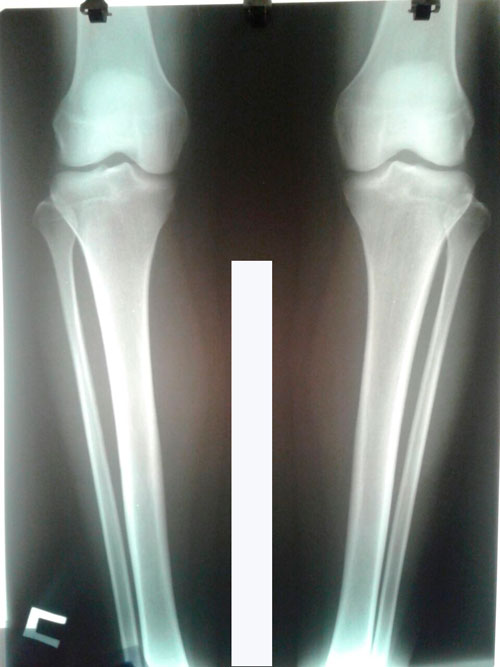

1,5 месяца с момента снятия аппаратов.

Всё в норме!

Физическая нагрузка по нарастающей, каблучки по нарастающей (от меньшего к более высоким), беременеть через 6 месяцев.